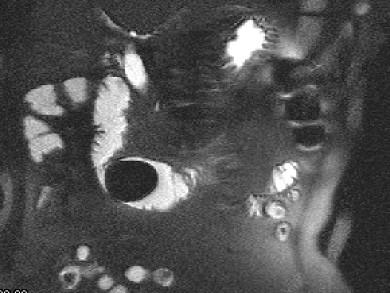

女 ,80岁 ,右上腹疼痛反复发作 6个月,加重 2天 ,曾有胆囊炎及胆结石病史,影像检查如图,应诊断为 ( ) WXJ-04341.jpg WXJ-04342.jpg WXJ-04343.jpg

• A.十二指肠巨大胆结石(胆囊十二指肠瘘)